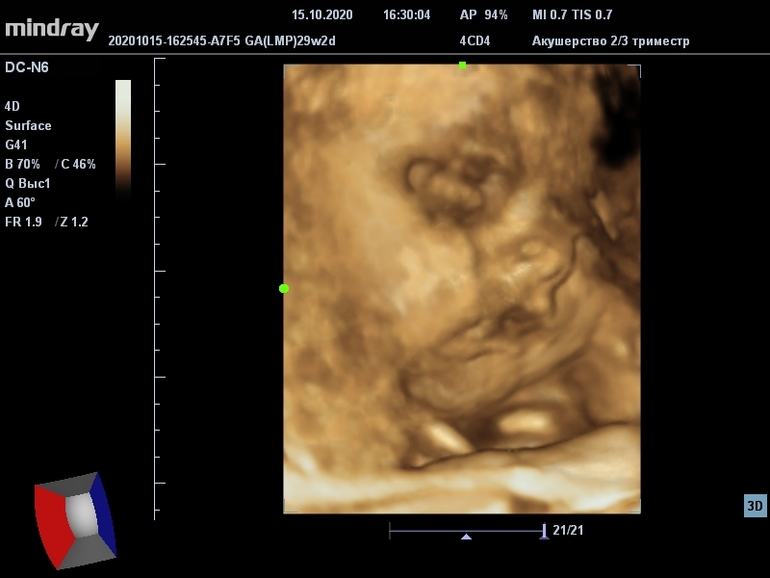

В 28 ровно были с мужем на 3Д УЗИ, уточню, что это была попытка номер 2, до этого пошли в 27 ровно, малыш был в тазовом, подмял под себя ручки, ножки и пуповину, весь спрятался🤷♀️ Врач решила, что так дело не пойдёт, не взяла с нас денег, переписала через неделю и сказала, делать упражнения, чтобы малыш в идеале перевернулся в головное) Пару дней я поделала упражнения, а потом у нас были сборы и переезд, я много наклонялась, собирала вещи, потом так же их разбирала, активничала и мне показалось, что малыш перевернулся, потому что движения и толчки стали совсем другие) И да! УЗИ нам это подтвердило)

Здорово было побывать с мужем, он впервые видел всё это в живую, интересно, конечно)) Первый раз мне сказали, что малыш немного опережает даже, до этого день в день шёл) Поставила 28-29 недель. Сладкий мальчик весит 1350 уже, такой щекастый, постоянно улыбался, врач сказала : "Весёлый парень😁", ну, это у нас есть в кого))) Пытались понять, чей же носик, потому что по обычному УЗИ на скрининге по профилю решили, что мужа, а теперь показался, что мой, ну, или свой собственный😁

Думала, что фоточки будут немного лучше, ну, пойдёт на память😁 Сказала, что очень активный для этого срока уже) Не могли поймать кадр.